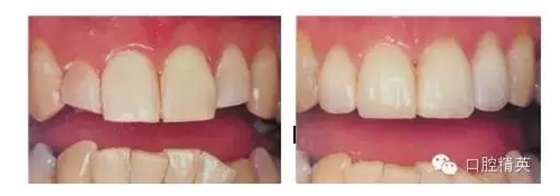

這是一個30歲左右的一個女士,她就是原來上前牙顏色不太好看,上頜三到三做一個樹脂貼面,但是樹脂貼面隨著時間增長,有部分的脫落,還有邊緣的著色,所以她就是,因為她是在做一個銷售方面的工作,她說我這個牙做銷售,這個口有時候真不好張,所以就覺得,因為你要做銷售每天面對一定的顧客,而你每天必須說很多很多的話,但是這個牙齒能很影響她自己的工作,所以她就需要,非常的需要,及時把我這個牙齒做的,但她也有一個要求,她說我做完以后我不想讓人知道就是說我做牙齒了,但是我又想讓它做的好看一點,又不想讓別人發(fā)現(xiàn),所以這當時也是一個比較難以實現(xiàn)的問題,所以我們就當是考慮,如果要做的話,這個顏色要跟旁邊的鄰牙和下牙要相協(xié)調(diào),顏色不用太白了,太白了就顯得比較突出,患者可能就不能接受,所以我們在選擇顏色上面來做一些考慮,所以我們就把她的樹脂貼面磨出以后,還是考慮做上頜三到三的一個瓷貼面修復。這是我們修復完成以后的情況,大家可以看看上面三到三我們做全瓷貼面修復,然后顏色上要白一些,就是說比下牙要白一點,但是也不是特別亮白。她后來復查的時候說她們的同事,就是做完牙以后上班,然后見到同事,同事就說,哎呀你這個是變化,但是就是說不知道是那塊變了,所以這種心里,同事這句話以后,她說了她心里特別高興,然后她就會,她告訴我,就是說復查以后她告訴,說這個特別滿意,就是說我做我前牙的這個美容修復,我達到了我需要的效果,所以這樣以后,她覺得自己花費了一定費用,覺得是非常值當?shù)模疫@個修復體的邊緣你看看,就是顏色比較好,沒有邊緣著色,表面也比較光潔,相對于樹脂貼面就表現(xiàn)出了瓷貼面的優(yōu)越性。所以如果我們在有可能做貼面修復的時候,要多考慮一些瓷貼面的修復,而對于樹脂貼面的修復相對要考慮的少一些,就是從患者角度和修復的長期性來講,瓷貼面的長期性和美觀性還是要高于樹脂貼面的,我們樹脂貼面有它本身,有一些致命的問題是很難得以解決的。